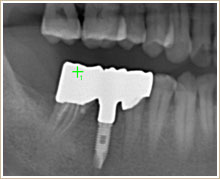

CTのデータや各種検査で適切な噛み合わせを診断します。

クラウンやインレーのやり変えとインプラントを1本入れています。歯列矯正はしなかったケースです。

クラウンやインレーのやり変えとインプラントを1本入れています。歯列矯正はしなかったケースです。